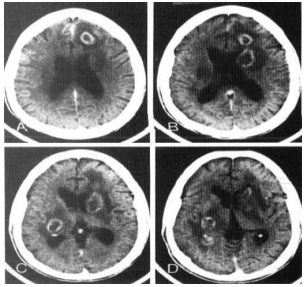

Mulher de 22 anos de idade procurou o pronto-socorro com história de quatro dias de queda do estado geral, rebaixamento de nível de consciência e dois episódios de convulsões tônico-clônicas generalizadas. Exame neurológico na chegada mostrava hemiparesia à esquerda, Glasgow 13, sem sinais de irritação meníngea e com fundo de olho normal. Foi solicitada tomografia computadorizada de crânio, cujas imagens estão apresentadas a seguir. O médico da CCIH foi chamado para o parecer na conduta medicamentosa.

Considerando que a principal hipótese diagnóstica foi confirmada, qual deve ser a conduta?